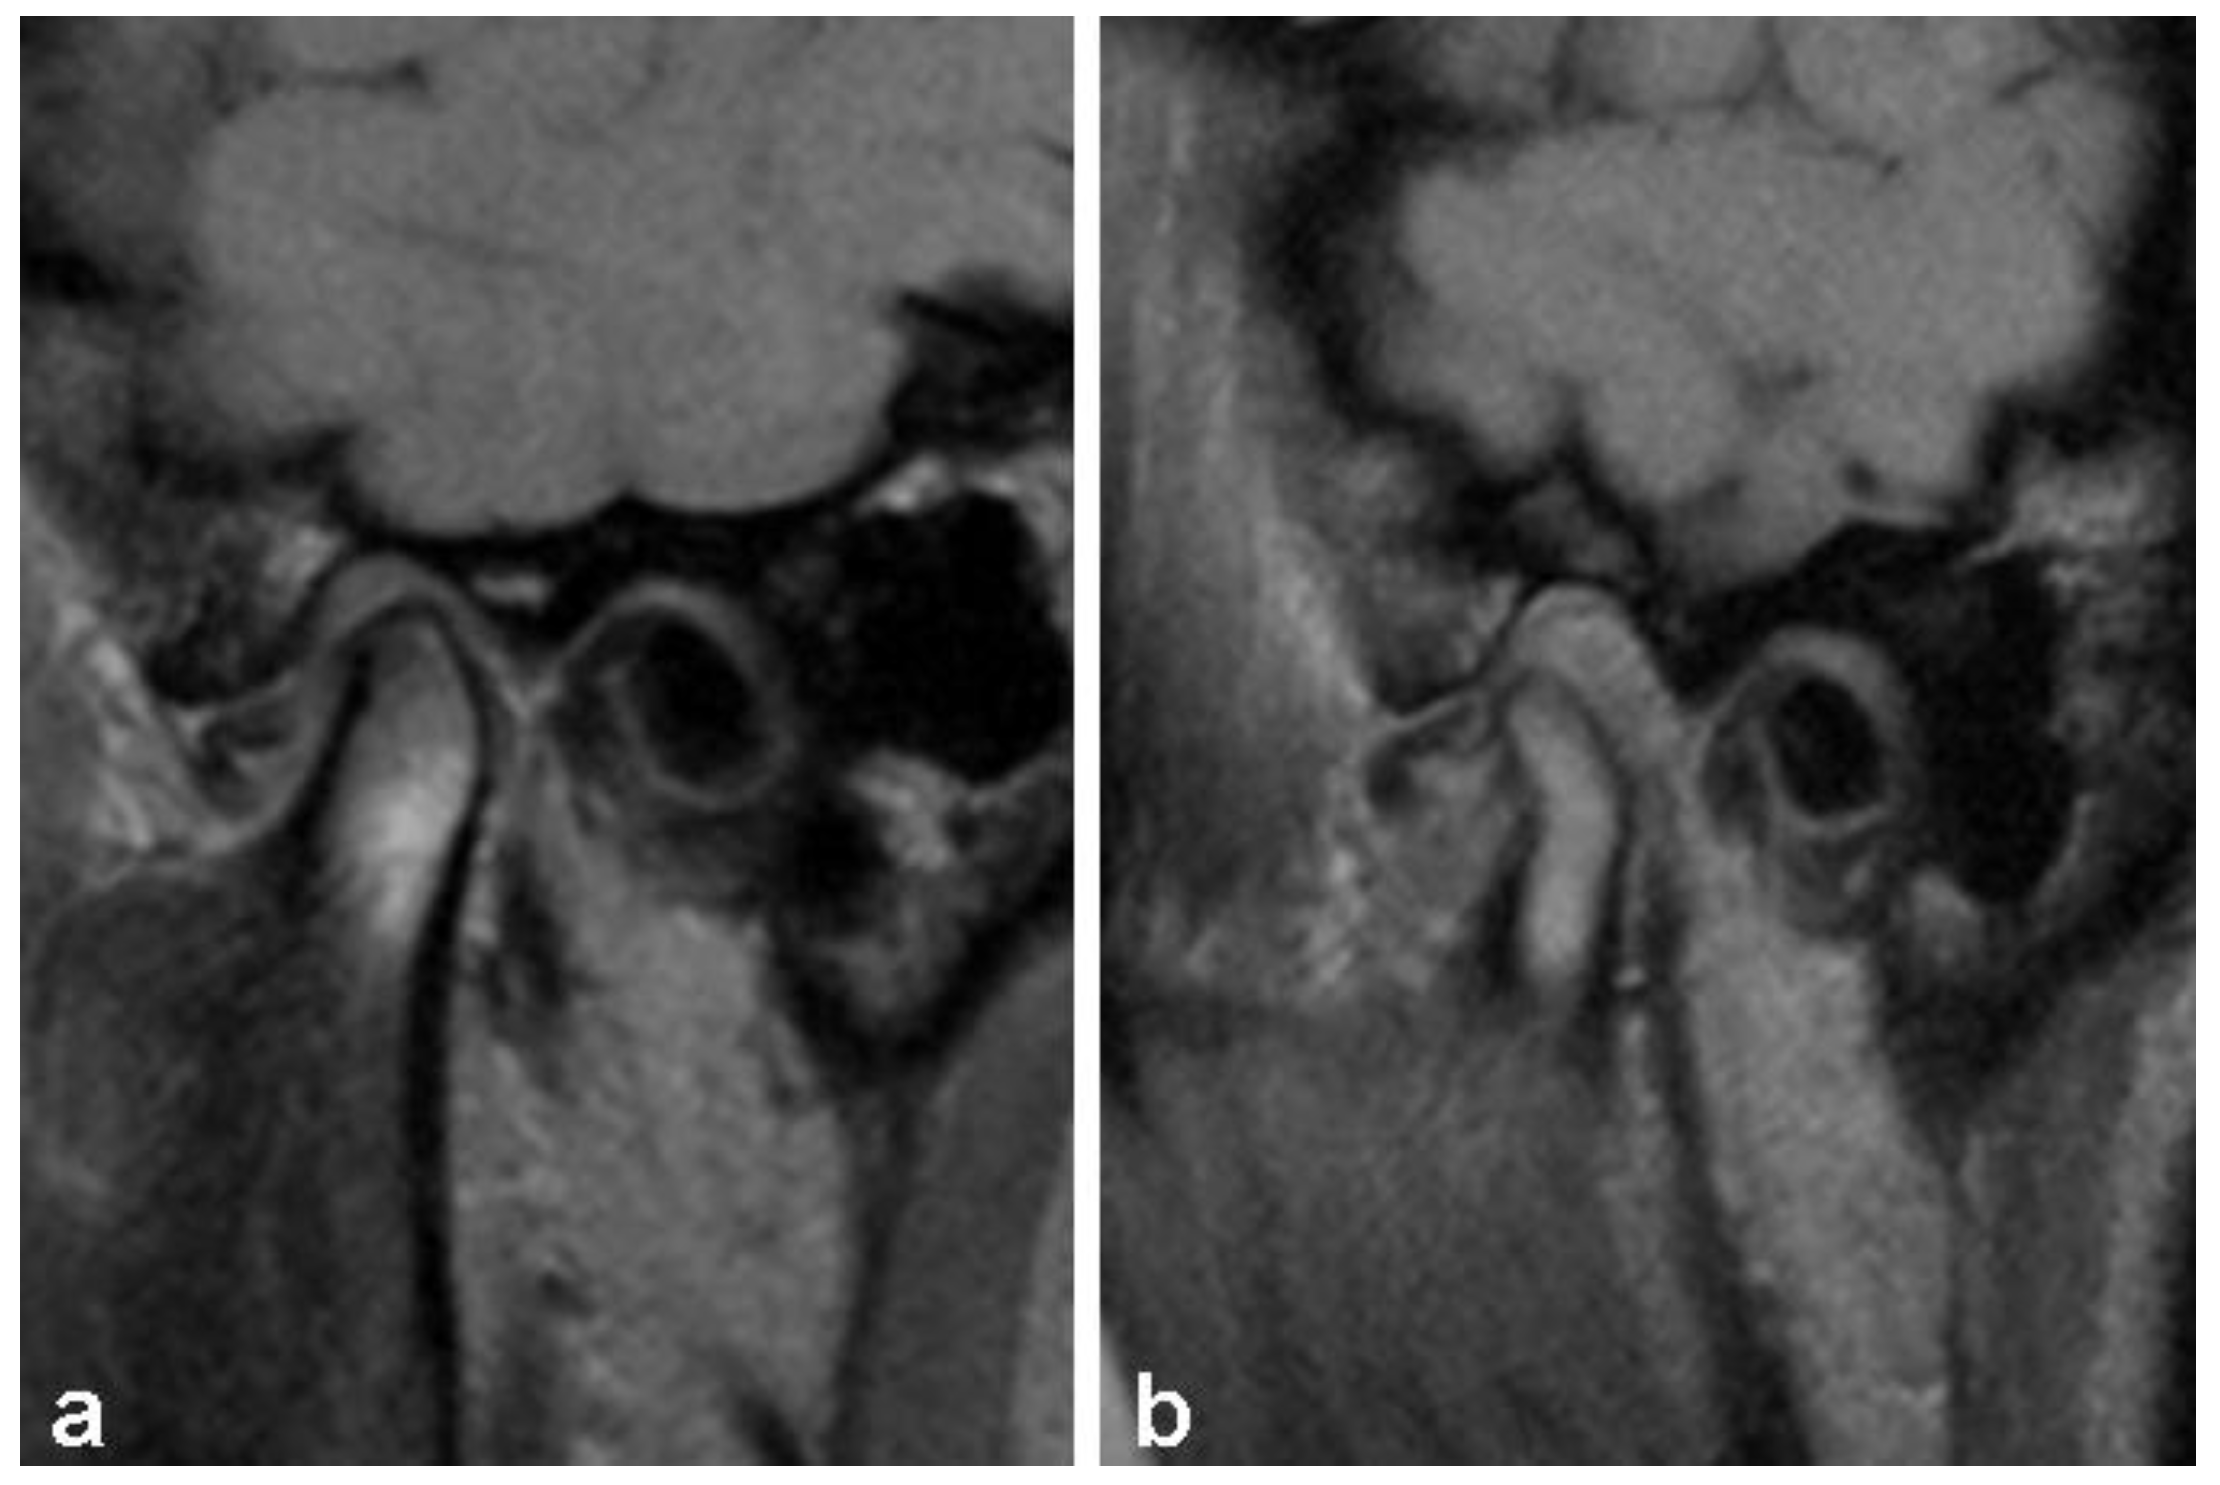

2.4. Analysis of TMJ